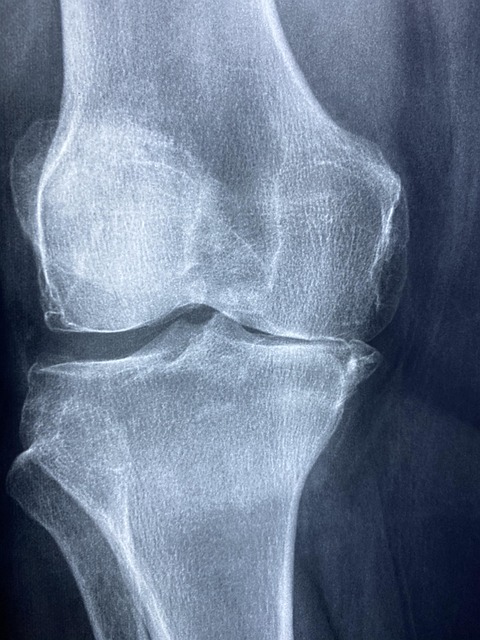

콘드로이친은 관절 연골의 주요 구성 성분으로, 골관절염 증상 완화에 도움을 주는 건강 보조제입니다. 임상 연구를 기반으로 한 정확한 콘드로이친 복용법을 알아보겠습니다.

무릎 골관절염 환자 604명을 대상으로 한 대규모 임상시험에서 콘드로이친 800mg을 하루 1회 복용한 결과:

- 6개월 후 통증 점수(VAS)가 42.6mm 감소했습니다

- 기능 및 통증 지표(Lequesne Index)가 4.7점 개선되었습니다

- 위약군 대비 통증 감소 효과가 9.3mm 더 컸습니다(p=0.001)